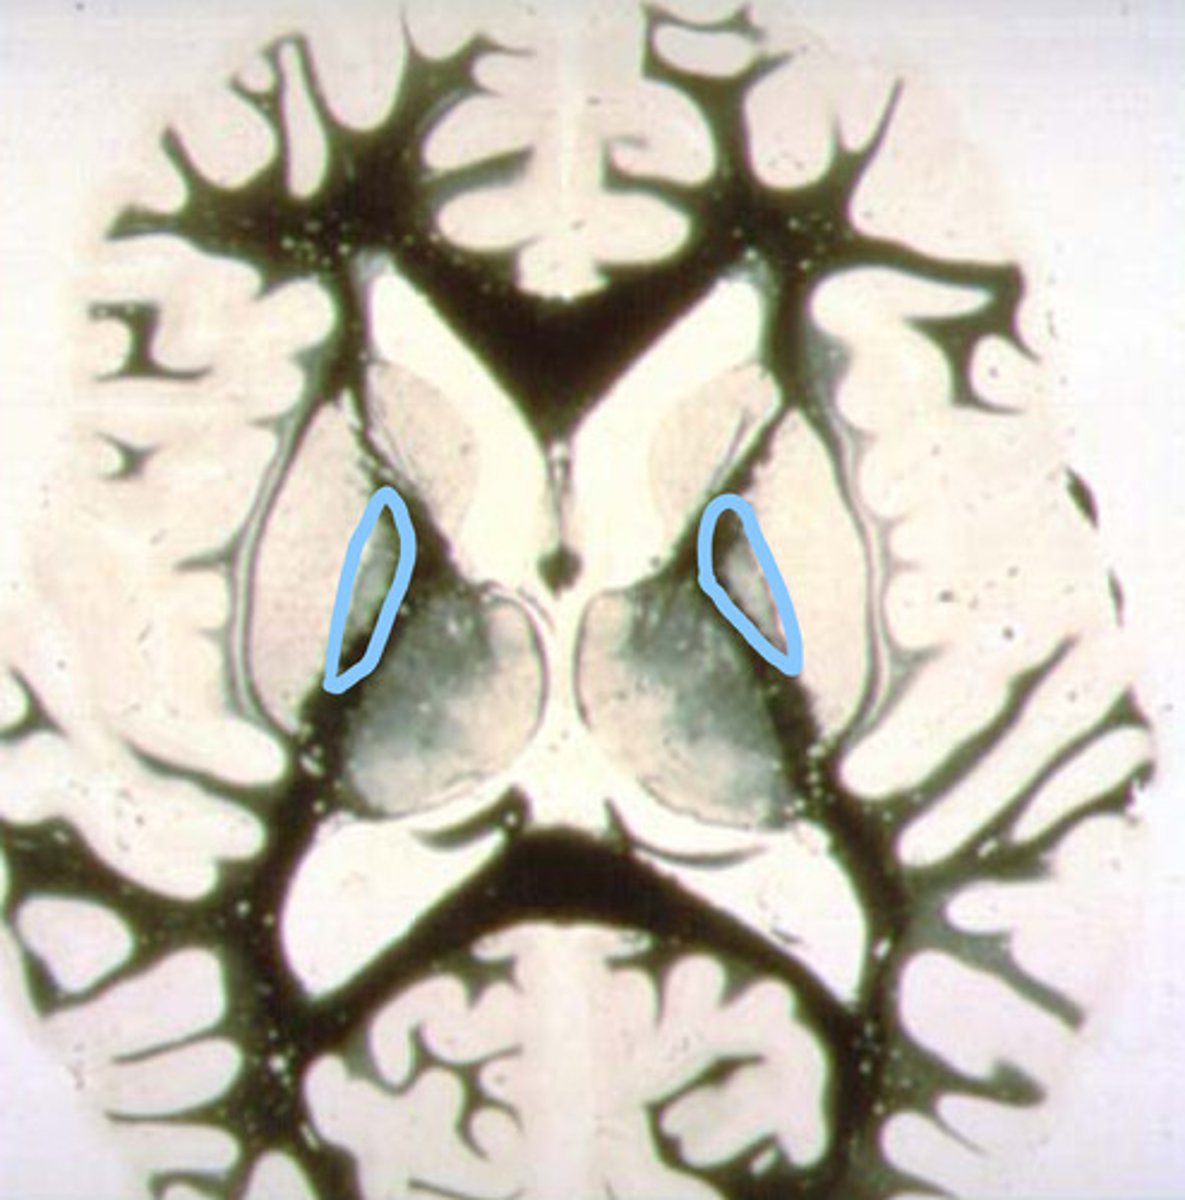

head of the caudate nucleus

identify the structure

putamen